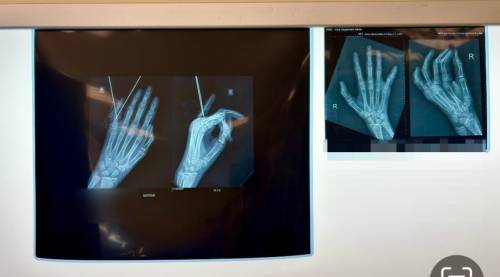

12-летний мальчик упал, катаясь на велосипеде, его рука попала в узкое пространство между планками забора. Как сообщили в Минздраве Приморья, врачи диагностировали —  закрытый, многооскольчатый, внутрисуставной перелом мизинца. Хрупкая косточка у основания пальца раскололась на несколько частей прямо внутри сустава. Если её просто загипсовать, осколки могут срастись неправильно, и палец перестанет сгибаться.

«Такой перелом опасен высоким риском нарушения функции сустава, что в будущем могло бы привести к тугоподвижности, деформации пальца и болезненным ощущениям при движении.

Учитывая характер перелома, было принято решение о фиксации пальца аппаратом наружной фиксации», — поясняет заведующая детским травматологическим отделением Евгения Кудинова.

Через микроразрезы были установлены спицы, которые соединили костные отломки и зафиксировали их в правильном анатомическом положении до полного сращения.